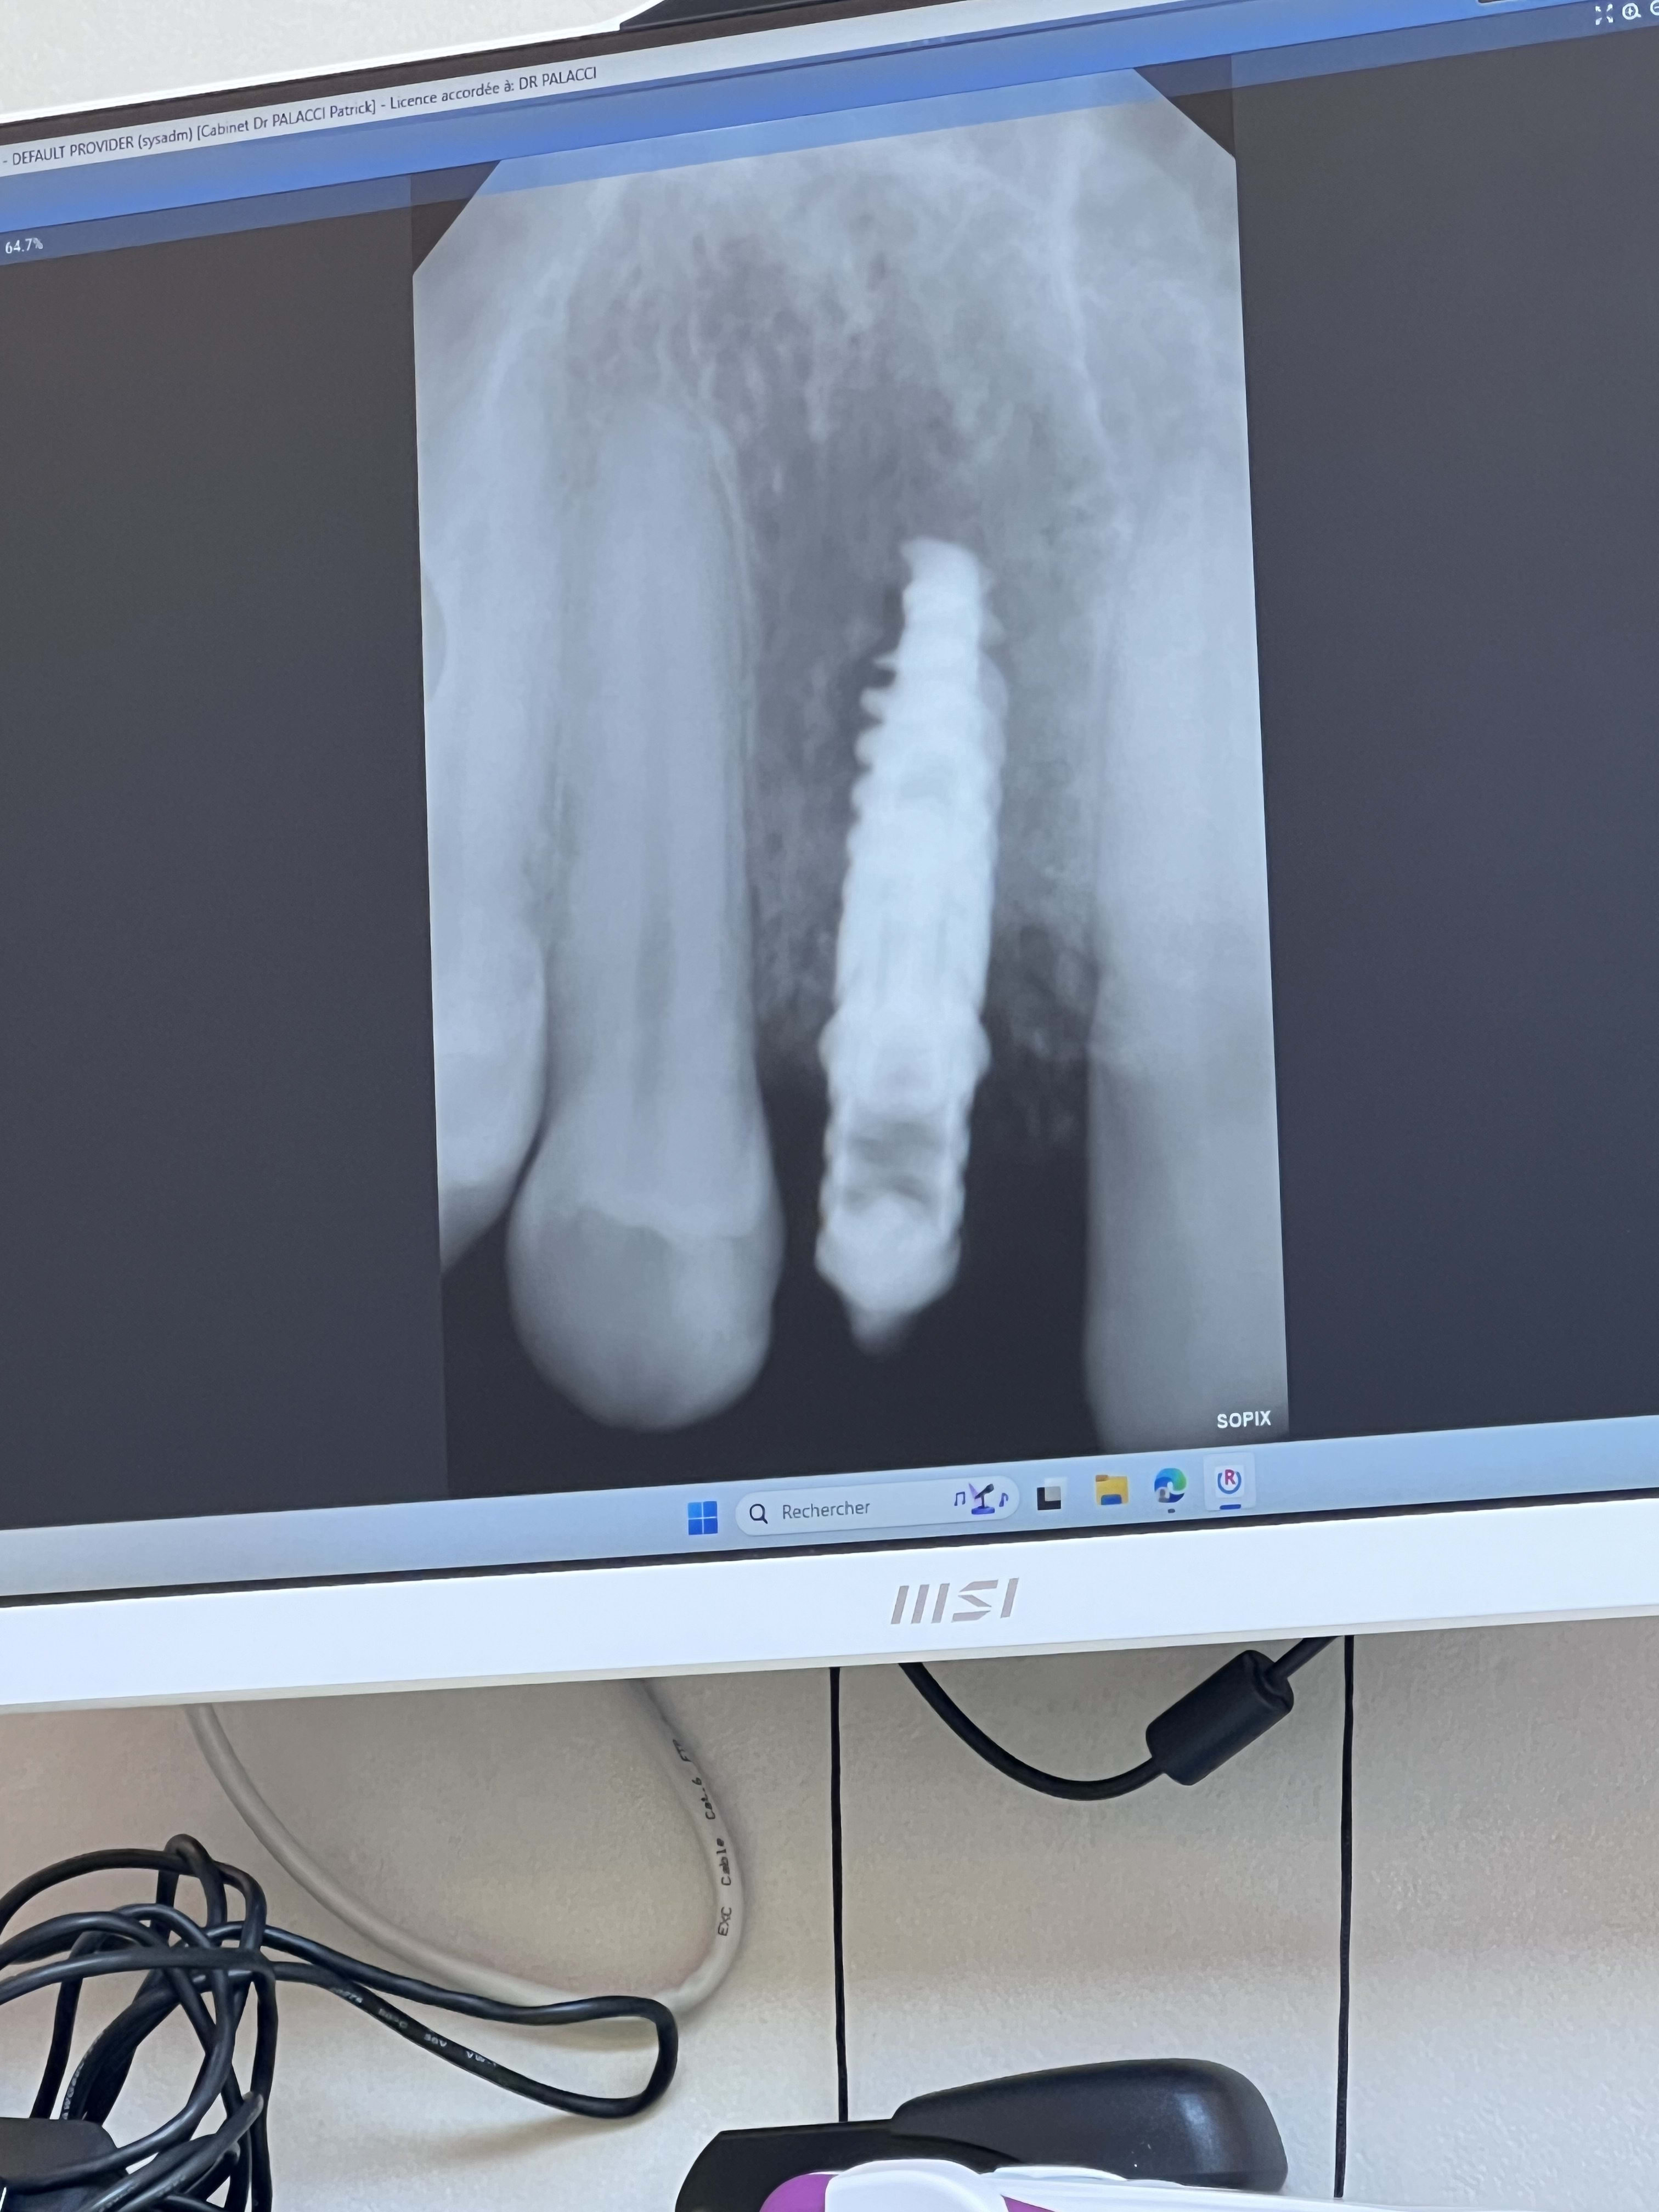

J’ai un problème suite à la pose d’un implant en 12 avec une mise en charge immédiate.

9 mois après toujours les mêmes douleurs lors de pression latéral

Implant qui a une très légère mobilité

Image présente à la radio.